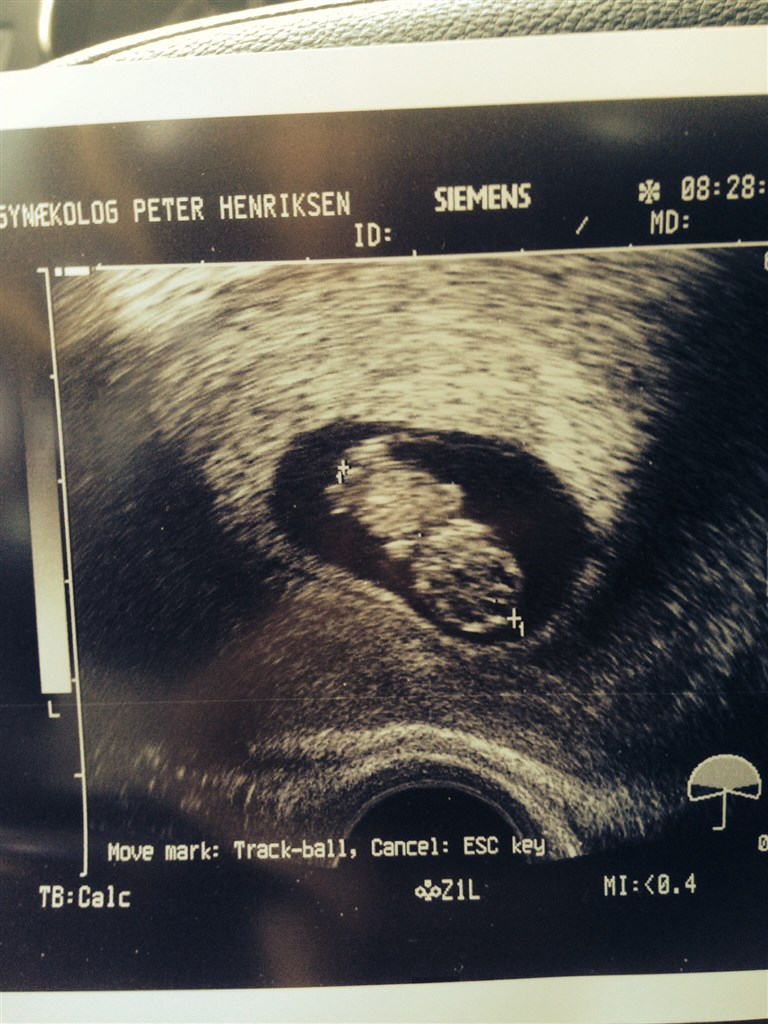

Så er det ikke mere lykkelig og kom til scanning og se enes lille fisk og et flot hjerte som banker og den har fået arme, ben og den hygge sig<3<3

22 mm ren kærlighed

Mor og far glæder sig til og se dig til NF